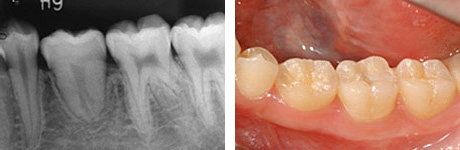

移植後3年。

移植後6年。